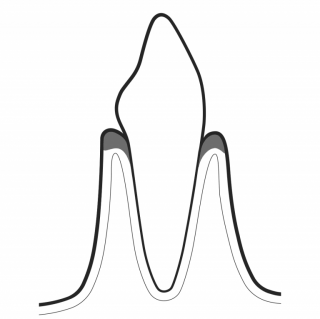

TREAT PERIODONTITIS

PERIOFLOW® with PLUS Powder preserves cementum during periodontal maintenance. It effectively removes subgingival biofilm in residual deep pockets. The PIEZON® PS NO PAIN Instrument removes the remaining calculus in a minimally invasive way. Final check ensures that no calculus remains.